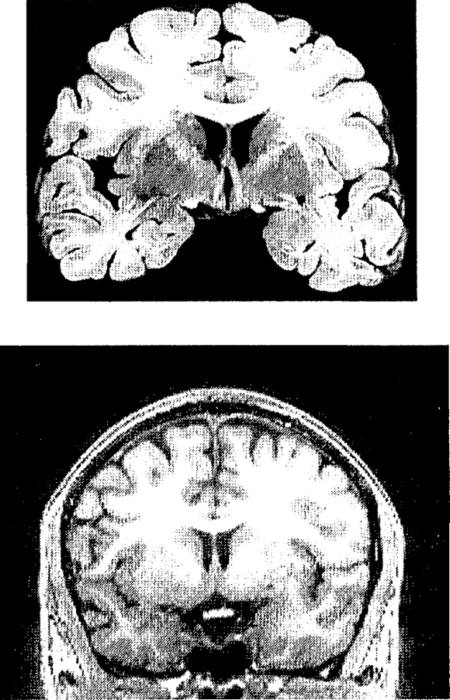

Через несколько лет был разработан другой метод, еще лучше прежнего, – магнитно-резонансная томография (МРТ). В МРТ используются не рентгеновские лучи, а радиоволны и очень сильное магнитное поле. [15] В отличие от рентгеноскопии эта процедура совершенно не опасна для здоровья. МРТ-сканер намного чувствительнее к различиям плотности, чем АКТ-сканер. На изображениях мозга живого человека, получаемых с его помощью, различимы разные типы тканей. Качества таких изображений не ниже, чем качество фотографий мозга, после смерти извлеченного из черепа, законсервированного химикатами и нарезанного тонкими слоями.

Рис. п.2. Пример полученного с помощью МРТ структурного изображения мозга и срез мозга, извлеченного из трупа.

Вверху – фотография одного из срезов мозга, извлеченного из черепа после смерти и нарезанного тонкими слоями. Внизу – изображение одного из слоев мозга живого человека, полученное методом магнитно-резонансной томографии (МРТ).